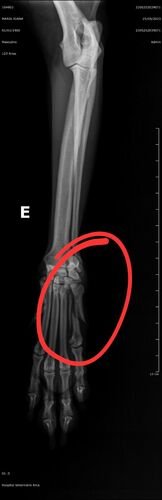

Meu nome é Giovanna, minha cachorrinha Maria Joana sofreu uma picada de cobra e também acabou fraturando a patinha da frente.

Hoje recebi o retorno do ortopedista/veterinário com os custos da cirurgia pra resolver a patinha dela e infelizmente não tem pra onde eu correr. Não tenho mais limite no cartão para estar passando a cirurgia. E a vista também nao estarei conseguindo pagar.